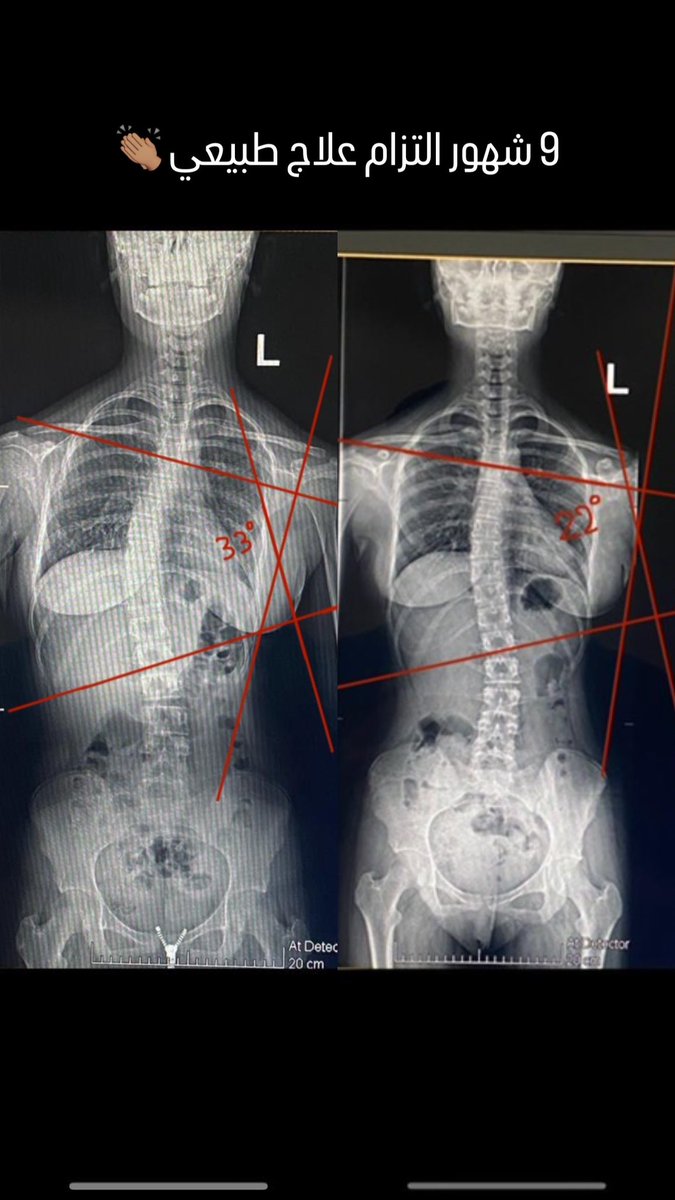

العلاج الطبيعي المتخصص لمشكلة الجنف‼️ مفيد وفعال جدا مع الحالات المتوسطة الى الخفيفة. يفضل عدم اتباع نظام المتابعة فقط خصوصا إذا كان العمر تقريبا ١٣-١٤ سنه وأصغر. نتائج مبهرة ومرضية لالتزام ممتاز مدته ٩ شهور 👏🏽

العلاج الطبيعي المتخصص لمشكلة الجنف‼️

مفيد وفعال جدا مع الحالات المتوسطة الى الخفيفة.

يفضل عدم اتباع نظام المتابعة فقط خصوصا إذا كان العمر تقريبا ١٣-١٤ سنه وأصغر.

نتائج مبهرة ومرضية لالتزام ممتاز مدته ٩ شهور 👏🏽